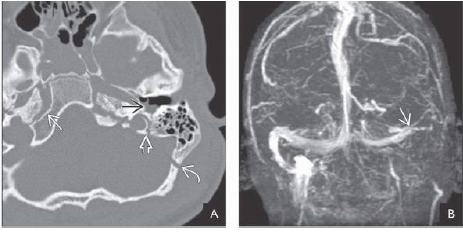

What sign is shown in this pt with EDH?

EDH with depressed skull fracture lacerating the middle meningeal artery . Inset shows

rapid bleeding, “swirl” sign